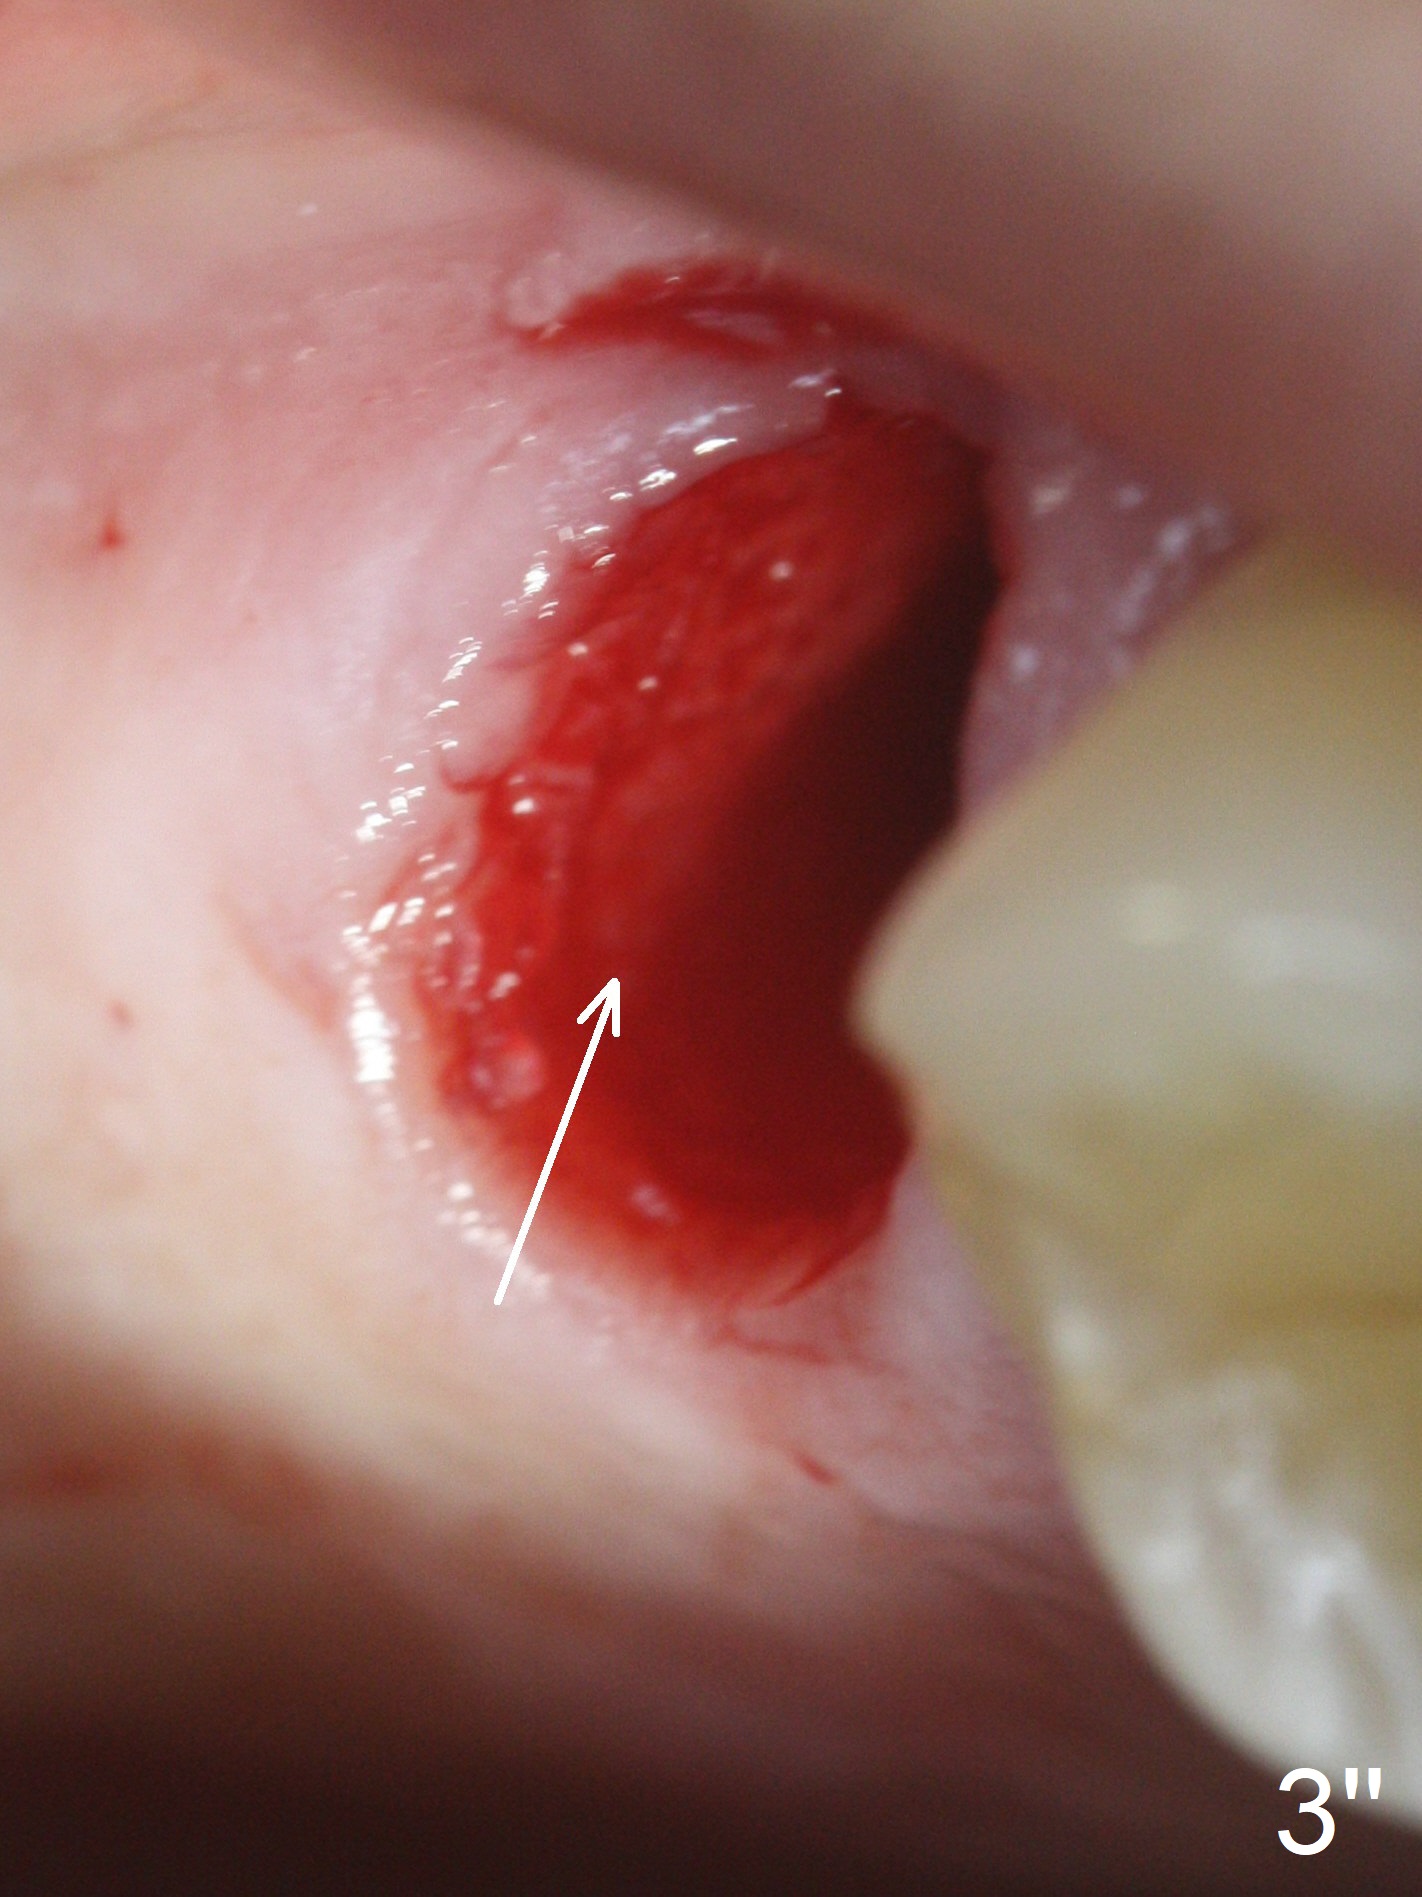

The palatal cusp of the affected 2nd premolar is apparently rotated distal (Fig.1). It is more obvious for the socket (Fig.2): the palatal (P) portion of the socket is more distal than the buccal (B) one. When the gauze is removed (Fig.3), Lindamann bur is used to remove the disto(D)palatal bone of the socket (data not shown), followed by starter drill in the DP wall obliquely (Fig.3'). Once the drill enters the bone for 1-2 mm, the bur is straightened and pushed slightly distal (Fig.3''). Fig.4 shows a parallel pin distal (overcorrect) to the original socket (Fig.4 red dashed line). Sequential osteotomy is conducted until 3.8x13 mm drill for 18 mm (Fig.5): note the 2 steps of the osteotomy (red lines). Since the apical portion of the osteotomy is larger than the drill, a larger implant than expected (5x16 mm) is placed. The implant ends up in the middle of the edentulous area (due to the stepped osteotomy; Fig.6-9; >60 Ncm). Vera allograft is placed (Fig.7-9 *) prior to and after placement of a 6.5x4(3) mm abutment (Fig.8-10). The remaining socket opening is sealed with a piece of Collagen plug (Fig.10 *). The socket is then closed by an immediate provisional (Fig.11 P). The abutment is retightened 2 months postop (Fig.12,13). The crown is cemented 4.5 months postop. Panoramic X-ray and CT are taken nearly 7 months post cementation (Fig.14,15) when the patient is ready for #30 implant guide preparation.